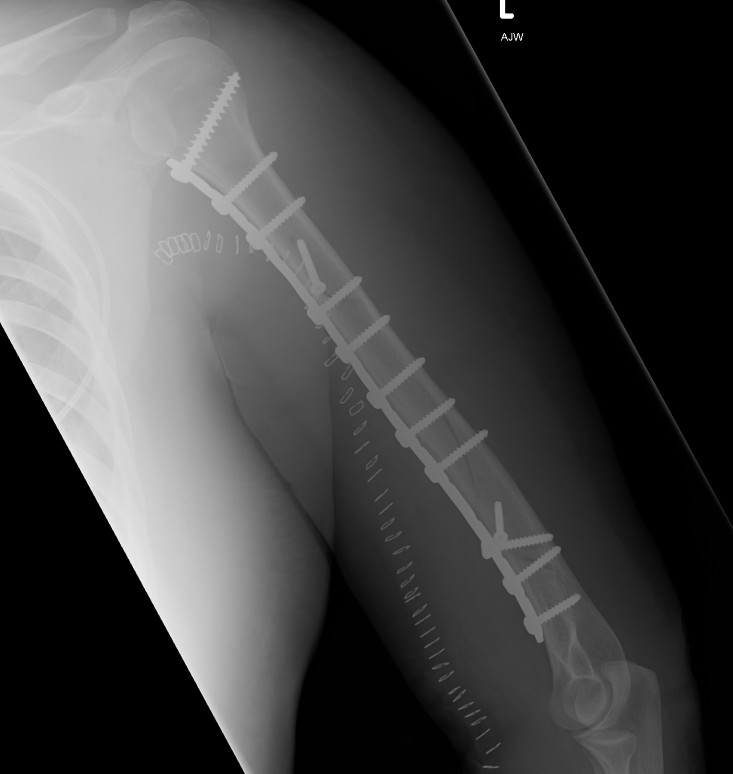

Humeral Fracture SegmentalHumeral Plate LateralHumeral Plate Long AP

Segmental fracture ORIF

Prox humerus 1Prox humerus 2Prox humerus ORIFProximal humerus ORIF

Proximal third humerus ORIF of nonunion